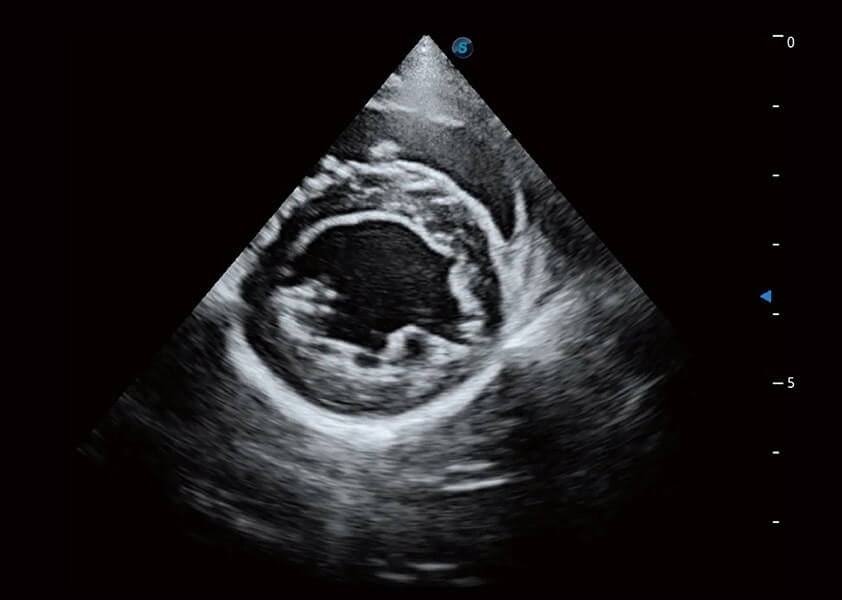

心脏解决方案

ProPet 60 配备了丰富的心脏探头群、先进的成像技术和专业的心脏测量工具,可帮助动物医生为不同体型和生理结构的动物提供心脏和心肌功能的全面评估。

优异的基础图像

(犬)乳头肌短轴